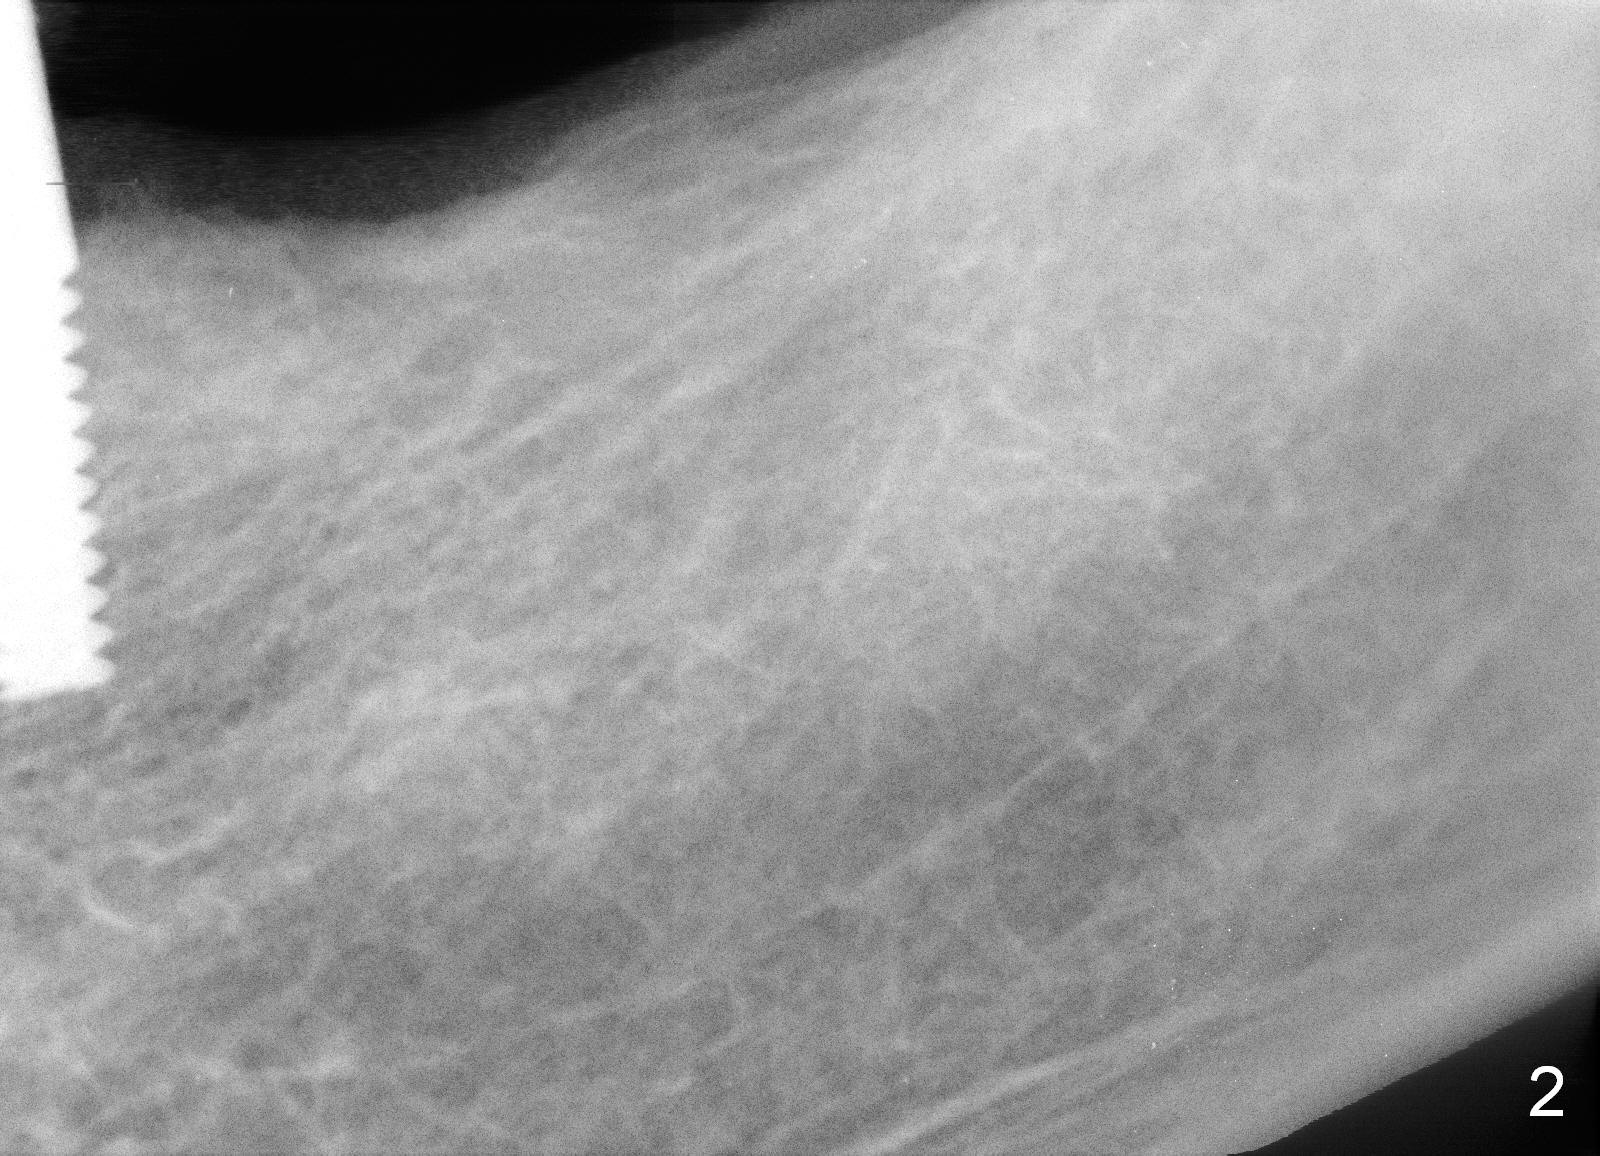

Last visit, a 76-year-old lady found that the tooth #24 was mobile. After #25 implant crown recementation, occlusal equilibrium was done so that occlsual force/contact was transferred from #24 to #25. Two weeks later, the tooth #24 mobility is reduced. The patient wants to crown the rest of the lower anterior teeth. After discussion, she agrees to restore the posterior teeth first. PAs and impression are taken (Fig.1-4). When the implant was placed at the site of #20 (Fig.1), the bone was found to be soft. To obtain primary stability, osteotomy at #18 and 19 will be under prepared (one size smaller). The immediate provisional at the site of #20 is oversized mesiodistally. Before surgery, it should be trimmed as shown in Fig.4 red dashed line. The 3 implants are to be splinted. No localized use of antibiotic is for this case, since these 2 teeth have been missing > 6 months.